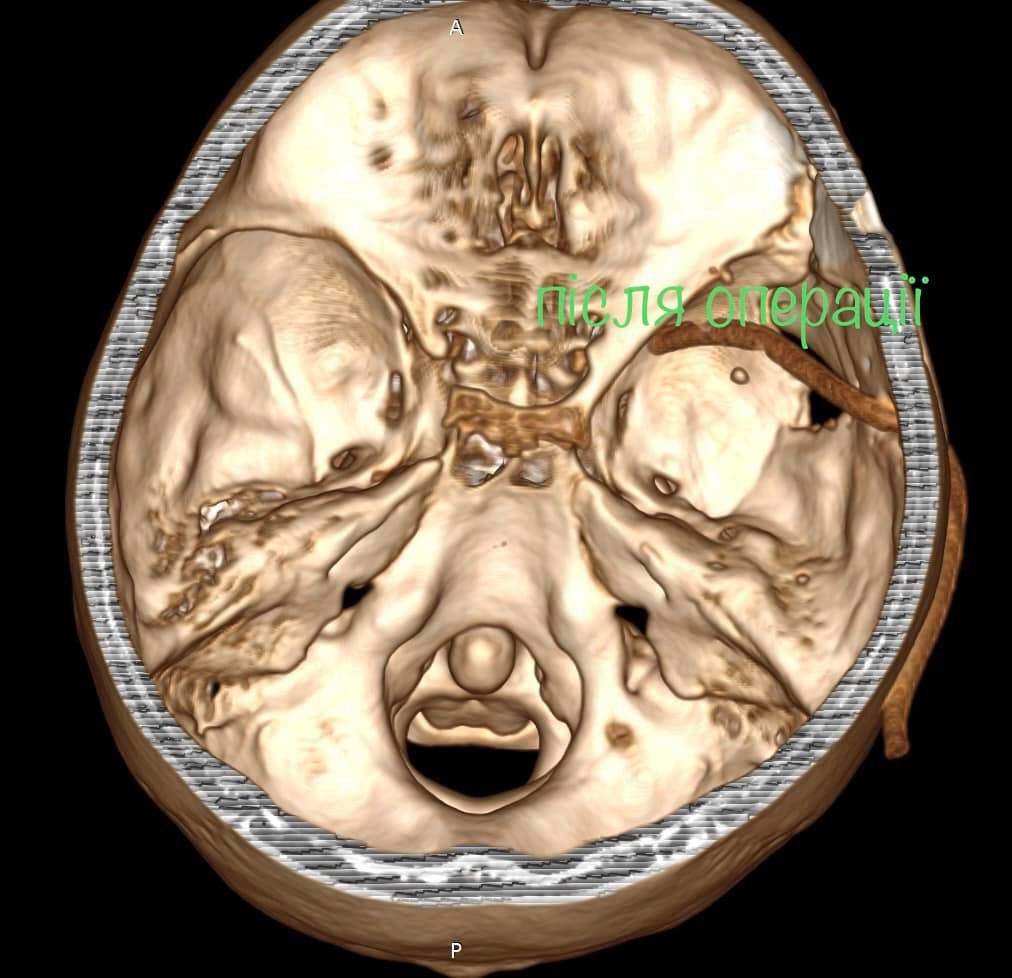

Як повідомив у Фейсбуці нейрохірург дитячої лікарні Михайло Ловга, у хлопця була куля в голові, що призвела до руйнації скроневої кістки та частини головного мозку.

«Ми виконали невідкладну операцію і вилучили стороннє тіло, видалили пошкоджені тканини і відновили цілісність збережених тканин. Добре, що куля зупинилась в 1 см від надзвичайно важливої судини і права скронева частка (яка пошкодилась в результаті травми) – функціонально незначима. Інакше, наш козак був би зовсім іншим, назавжди», – написав Михайло Ловга.